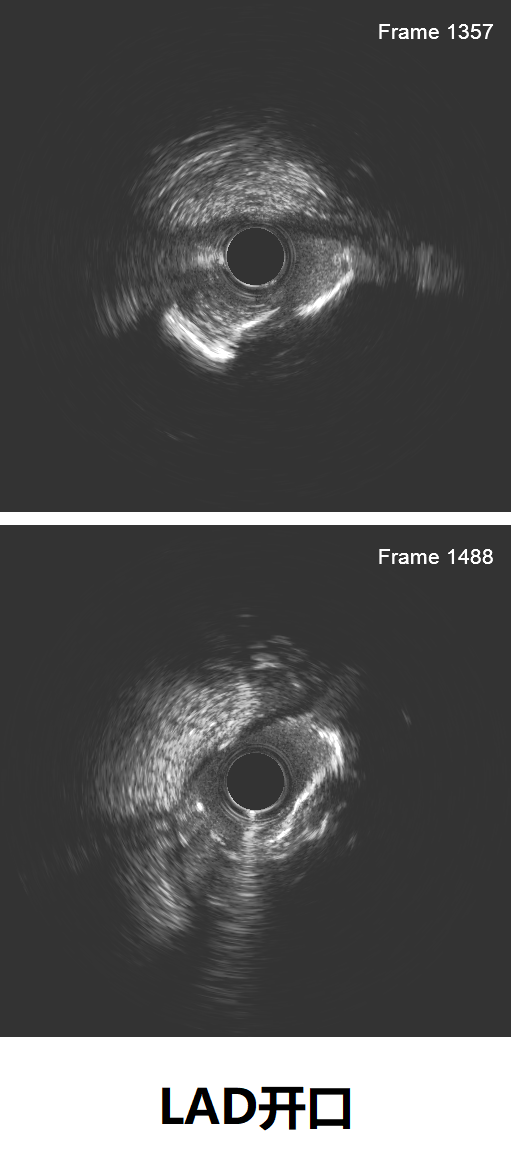

IVUS见左主干远段MLA:7.05mm²;前降支近段MLA:2.68mm²,中段MLA:2.63mm²,前降支近段至中段可见多发钙化小节突入管腔,局部90°-270°钙化,前降支开口至中段管腔直径约2.5-3.5mm,严重钙化段管腔直径约2.85-3.5mm。

根据IVUS结果,调整术式为精确定位前降支开口,预处理方式用3.0mm×12mm shockwave冠脉血管内冲击波导管。

复查IVUS提示前降支原近中段钙化斑块、钙化小节碎裂,未见明显夹层。